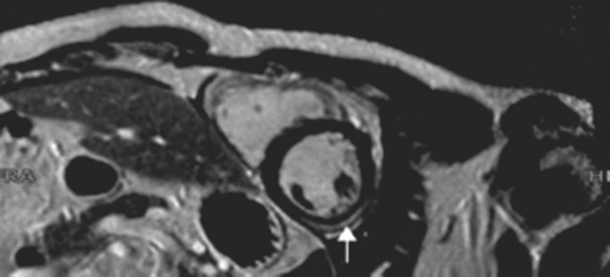

Fig. 2

MR image of the patient. The white arrow (gadolinium contrast) points to subepicardial inflammation of the midwall, the clue to the diagnosis of myocarditis

Cardiac magnetic resonance (CMR) changed the diagnosis of infarction into myocarditis of the midwall. In retrospect, several clinical features, including leukocytosis and elevated C-reactive protein, could have led to the diagnosis of myocarditis. Lifelong treatment with cardiac medication was prevented. Endomyocardial biopsy is the gold standard for diagnosing myocarditis; however due to its invasive approach it is not common practice [1]. CMR is an accepted diagnostic tool. Image analysis is limited by great clinical variance ranging from chest pain to fulminant heart failure [2, 3]. Using T1 and T2 sequences and late gadolineum enhancement, one can differentiate between myocardial infarction and myocarditis [1]. When Lake-Louise criteria are applied, sensitivity and specificity of CMR proved to be high compared to endomyocardial biopsy [14]. Viral myocarditis can induce myocardial ischaemia [1, 4]. The exact pathogenesis is unclear. Hypotheses state that ischaemia is a consequence of local endothelial dysfunction, coronary spasms and in situ thrombi formation [4, 5]. Specific epicardial lesions as are shown in Fig. 2 are proof of myocarditis. If no coronary stenosis is seen on CAG, myocarditis may be the cause.